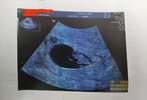

Znalazłam

Byłam 7+4. USG tego samego dnia, dwóch lekarzy i dwa sprzęty różne. Wg jednego 7+3, a drugiego 6+1. 🤣 Oczywiście najpierw miałam to gorsze i zryczalam się jak bóbr, szykowałam na poronienie i łyżeczkowanie 🤦 poleciałam szybko do super kliniki z super sprzętem i wszystko ok, maluch nie tylko mial serduszko, ale ruszał się... To było cudowne.

W każdym razie chodzi mi o to, że zobacz ile daje sam sprzęt. A do tego te maluchy w 6 tygodniu to mają koło pół centymetra. :D także na spokojnie. :)

• received_2965950250351245 (1).jpeg

received_2965950250351245 (1).jpeg

64,9 KB · Wyświetleń: 152